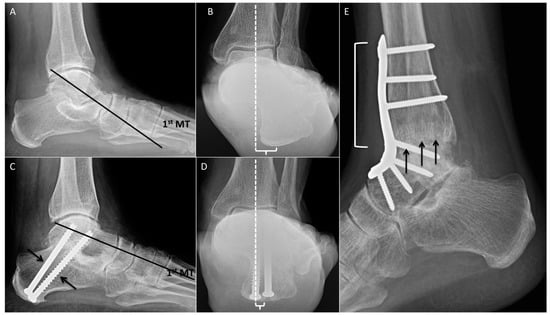

2.11. Calcaneal Osteotomy

2.12. Single-Plane Translational Osteotomy

2.13. Closing-Wedge Osteotomy

2.14. Rotational Osteotomy